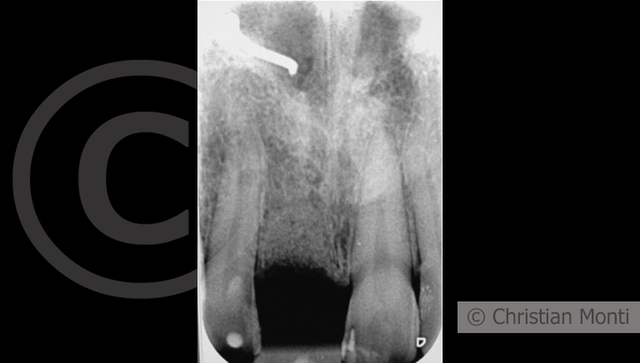

EDENTULIA SINGOLA

Impianto in sostituzione di un incisivo superiore